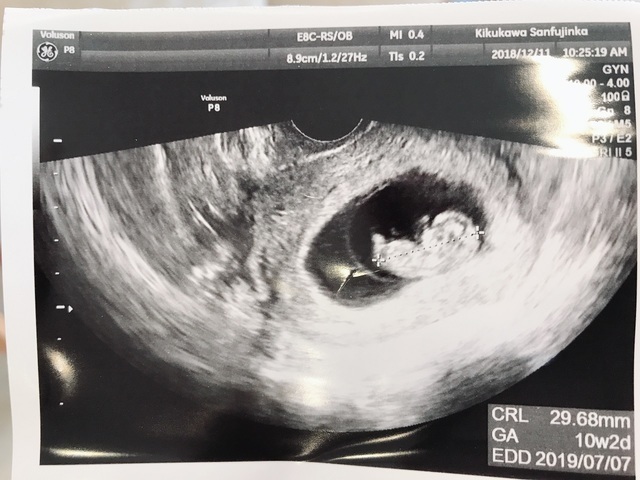

10週2日(10w2d・女の子)|みるたん さん(28歳)

エコー写真撮影時のエピソード:

10w2dでこのエコーを見て、手足が見えるようになって、自分の中に人間が入ってるんだなと実感することが出来た瞬間でした。

実親も主人もこのエコーを見てようやく妊娠を実感したようで、接し方が優しくなりました。